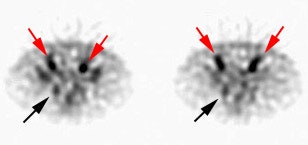

| Recurrent/metastatic prostate cancer: The patient below had a history of prostate cancer and a rising PSA level. A lymph node was identified in the posterior right pelvis on CT imaging (white arrow) and described as "borderline" abnormal by size criteria. A Prostascint examination was performed to further evaluate the finding. The Prostascint sudy demonstrated abnormal tracer uptake within the right pelvic node (black arrows), but no other sites of disease (red arrows indicate normal intravascular activity). Percutaneous biopsy of the node confirmed metastatic prostate cancer. |

|